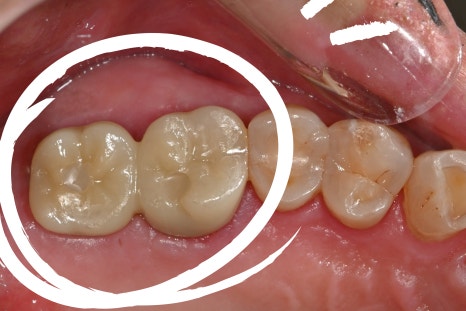

맞춤형 지대주 제작

임플란트의 마지막 단계는 보철(크라운)입니다.

겉으로 보이는 치아 형태가 완성되는 단계이지만,

실제로는 가장 섬세한 작업이 많이 들어갑니다.

교합(맞물림) 조정

잇몸과 보철물 사이의 밀착

주변 치아와의 높이·폭 조화

저작 방향에 따른 보철물 형태 조정

이 환자분은 맞물림이 한쪽으로 쏠리는 경향이 있어,

임플란트시술 보철 단계에서 이를 최대한

분산하는 방향으로 설계했습니다.

원내 기공소에서 스캔 데이터를 기반으로 맞춤 제작했고

장착 후에는 사진 촬영을 통해

잇몸과 보철물의 적합도를 다시 점검했습니다.